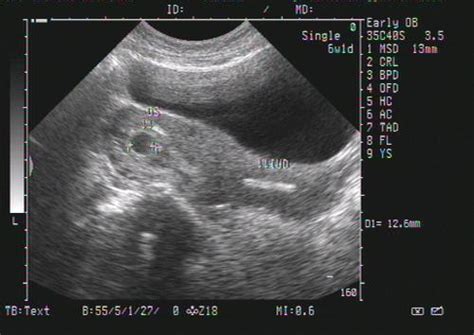

怀孕8个月的B超数据

根据孕周表,您的宝宝双顶径和骨长,也就是头部横径和大腿骨长都发育正常,胎心和羊水深度也在范围值内,脐带血阻比也正常。

不必担心,更不用提前剖腹产,完全可以顺产的。

怀孕8个月胎儿B超数据

怀孕八个月B超结果如下:双顶径80mm.胎心率132次/分,股骨长59mm,羊水深约61mm,内透声好。胎盘附于子宫前壁,厚约28mm,绒毛板轻度起伏。这样正常吗,知不知道有几斤?谢谢

31周左右,一切正常!